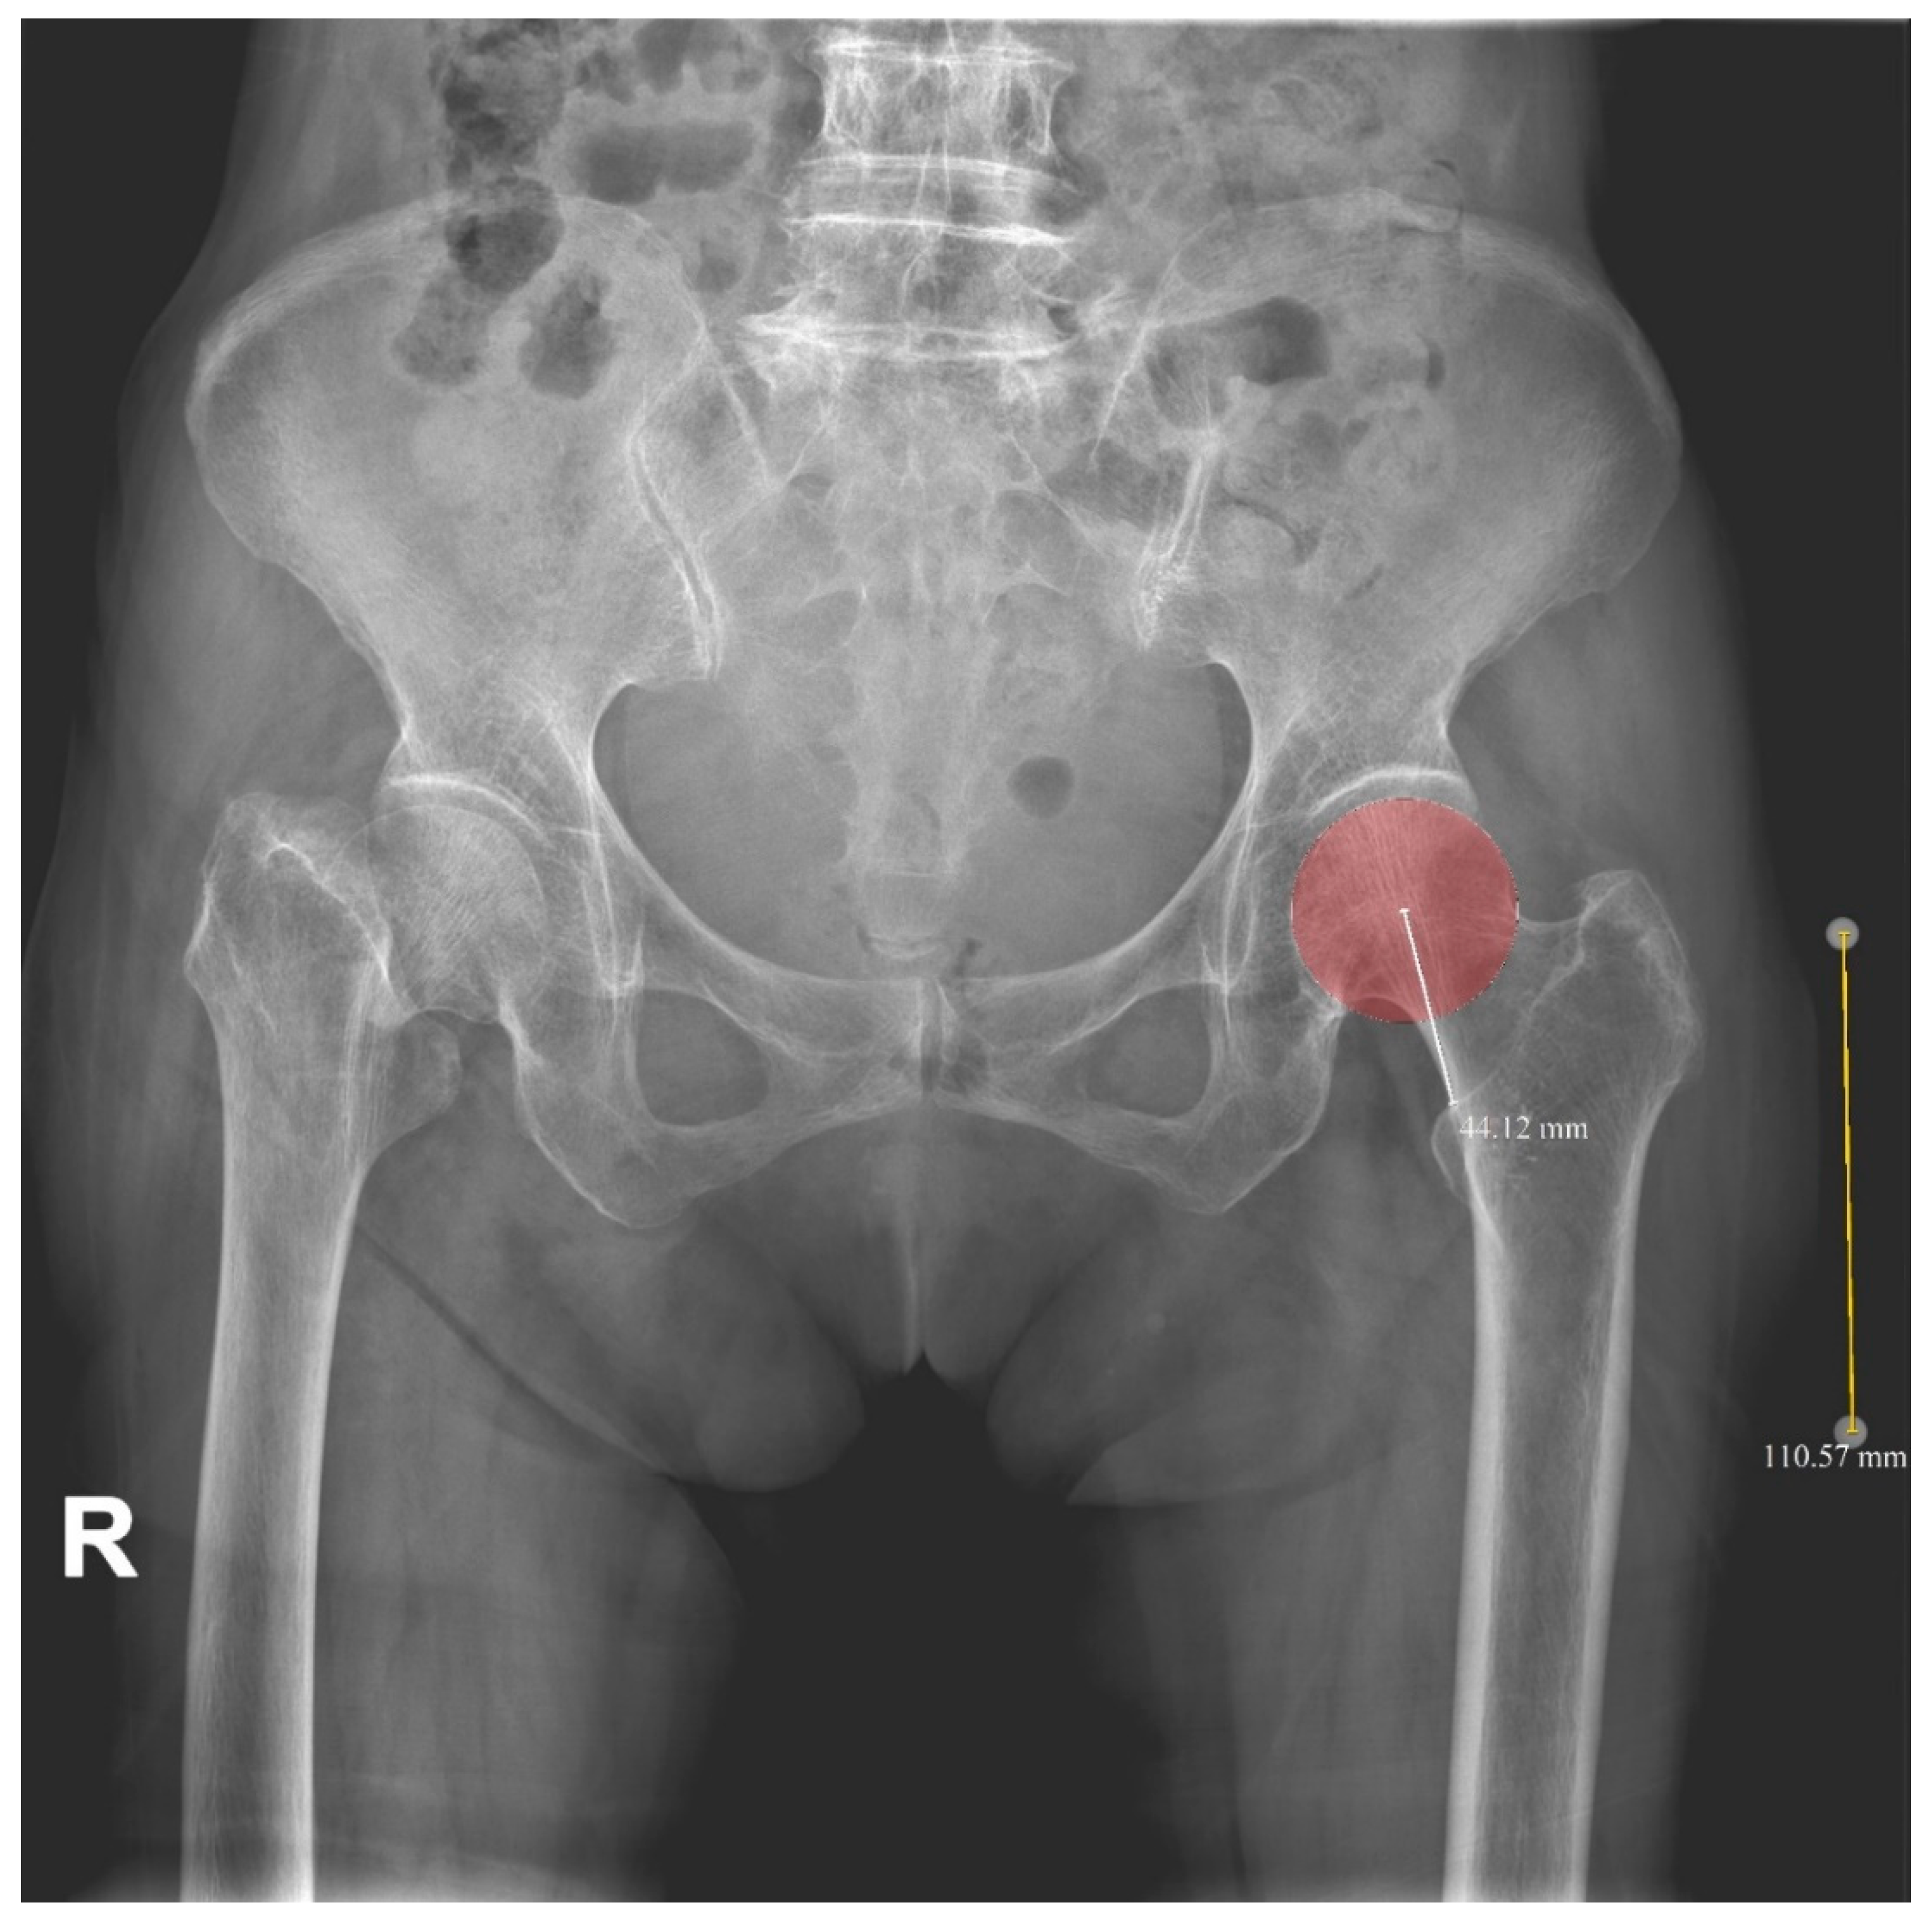

2.2. Radiologic Parameters